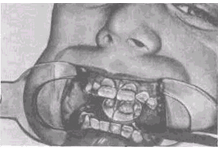

Различают несколько вариантов нормального П. (ортогнатический, прогенический, прямой, бипрогнатический). Они характеризуются смыканием зубных рядов на всем протяжении и отличаются друг от друга лишь особенностями смыкания функционально ориентированных групп зубов, в частности передних. Эталонным принято считать ортогнатический прикус (рис. 5, а), при котором верхний зубной ряд на всем протяжении перекрывает нижний, а во фронтальном участке верхние резцы перекрывают нижние не более чем на 1

/3

коронковой части зуба; между резцами верхней и нижней челюстей имеется режуще-бугорковый контакт. Прогенический прикус (рис. 5, б) отличается умеренным выстоянием нижнего зубного ряда. Прямой прикус (рис. 5, в) характеризуется тем, что верхние резцы не перекрывают нижние, а смыкаются режущими краями. При бипрогнатическом прикусе (рис. 5, г) верхние и нижние резцы наклонены в сторону преддверия рта, но между ними сохранен режуще-бугорковый контакт. Для всех вариантов нормального прикуса обязательным условием является нормальное функционирование зубочелюстной системы.

Рис. 5а). Схематическое изображение челюстей при основных разновидностях нормального прикуса (вид сбоку): ортогнатический прикус.

Рис. 5б). Схематическое изображение челюстей при основных разновидностях нормального прикуса (вид сбоку): прогенический прикус.

Рис. 5в). Схематическое изображение челюстей при основных разновидностях нормального прикуса (вид сбоку): прямой прикус.

Рис. 5г). Схематическое изображение челюстей при основных разновидностях нормального прикуса (вид сбоку): бипрогнатический прикус.